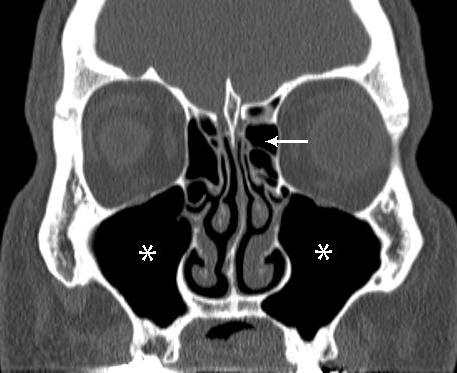

Как известно, синуситы подразделяются на несколько разновидностей. Наиболее распространённым считается воспаление гайморовой пазухи. Оно может быть как одно-, так и двухсторонним. Реже воспаление развивается в клиновидных (сфеноидит) и решётчатых пазухах (этмоидит). Также возможно инфицирование сразу всех перечисленных анатомических образований. Сочетанное воспаление пазух носа носит название пансинусит. Различить изменения на рентгенограмме удаётся не всегда. В этих случаях доктора рекомендуют выполнить МРТ пазух носа. Этот метод позволяет хорошо рассмотреть все ткани черепа. МРТ является диагностической процедурой, позволяющей послойно визуализировать органы и системы определённой анатомической области. На сегодняшний день данный метод считается одним из самых информативных способов выявления патологий. Компьютерная и магнитно-резонансная томография пазух носа позволяет увидеть изменения, которые нельзя рассмотреть никакими другими аппаратами для диагностики. Данные методы получили широкое применение во всех странах.

Только в случаях необходимости стоит назначать МРТ пазух носа. Что показывает данное обследование? Расшифровкой снимков занимает врач-рентгенолог или отоларинголог. По данным МРТ можно увидеть нарушение структуры тканей, тень от патологического образования и т. д. Благодаря данному методу диагностируют следующие патологии: